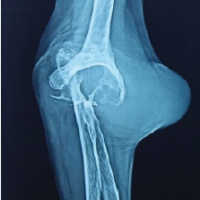

The patient was a 68-year-old male who had been diagnosed with type 2 diabetes, hypertension, and left leg peripheral arterial disease after a stent procedure in the left femoral artery. He first showed an infected left total knee prosthesis (Fig. 1).

Figure 1. Left knee after total knee arthroplasty. Anteroposterior and lateral radiographs demonstrating the left knee following primary total knee arthroplasty prior to the onset of infection.